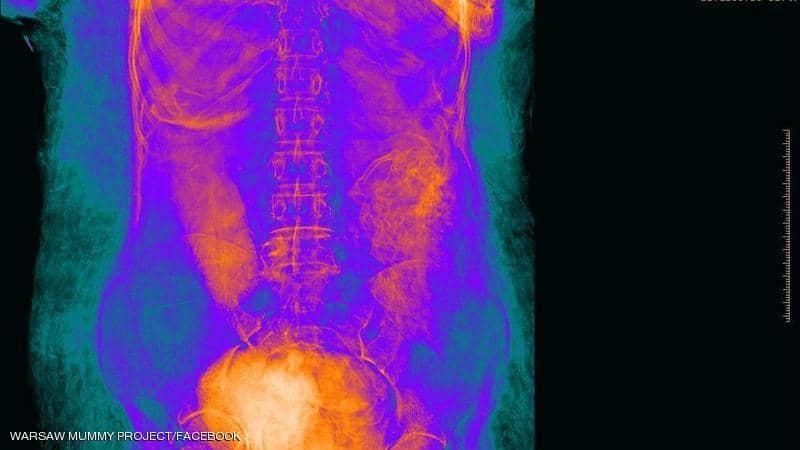

وتم إخضاع المومياء لعدة مجموعات من التصوير المقطعي والأشعة السينية وتصور ثلاثي الأبعاد مما سمح بفحص دقيق للجنين بأكمله والذي أثبت أن المرأة كانت في الأسبوع 26-28 من الحمل.